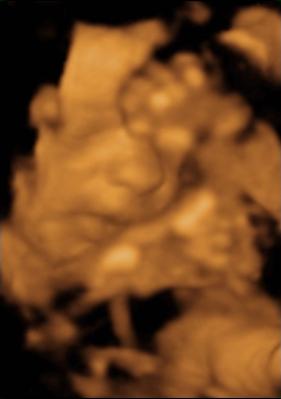

Fanni még farfekvéses 1,2 kg körül mozog és olyan cuki volt, mert a lábait az arca elé húzta és átkarolta őket. Mikor totál megunta, hogy böködik, akkor meg teljesen eltakarta a pofiját és bebújt a méhlepény felé.

na de azért hoztam pár képet!

Kép lábak, kezek és kislányalkatrész Kép az a gyönyörű bokacsont és vádli! Kép és a pofikája